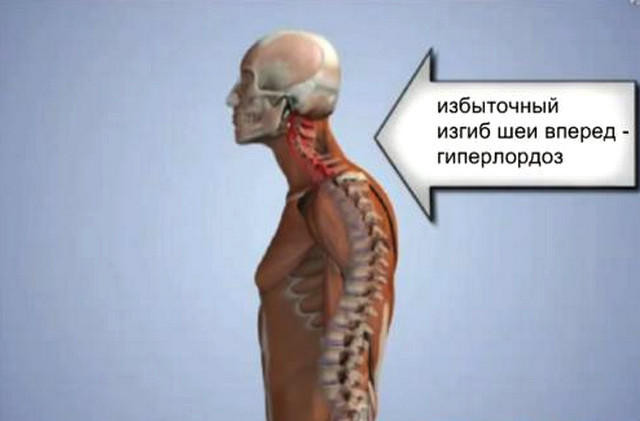

Искривление позвоночника: причины и последствия на снимках

Раздел: Визуальный дайджест